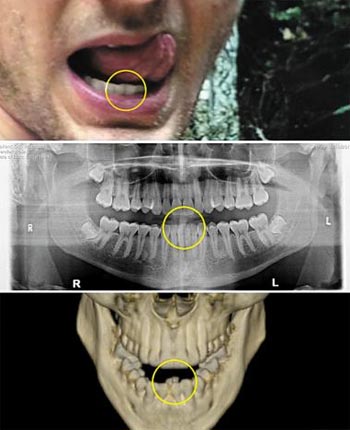

北朝鮮、故ワームビアさんをペンチと電気ショックで拷問か(1/1)